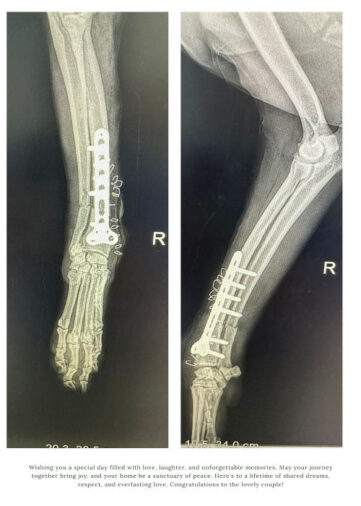

Last week, the hospital performed an orthopaedic surgery on a cat with a fractured leg. In cases like these, veterinarians perform bone pinning and bone plating just like in humans.

The surgical methods help fix broken legs by using pins or metal plates to hold the long bone in place, allowing it to heal properly and regain strength.

“In dogs and cats, the major surgery we provide is in the field of orthopaedic surgery, which includes the intermediary bone pinning and bone plating in terms of long bone fractures. For gastrointestinal surgery, the common condition in pets, let it be dog or a cat, is mainly a foreign body injection. So, sometimes there is a condition called intussusception where one intestine goes into the other intestine. So, in terms of gastrointestinal, we provide gastrotomy surgery,” said Dr Nima Wangdi, Deputy Chief Veterinary Officer, National Veterinary Hospital, Thimphu.